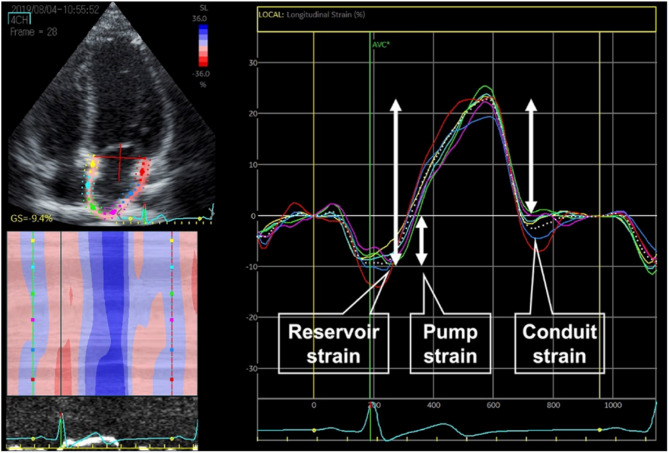

Methods: We analyzed three age-based subgroups of patients with rTOF (T1, T2, T3) and their corresponding healthy control groups (C1, C2, C3) to assess phasic left atrial function: T1 and C1 (3-9 years [children]), T2 and C2 (10-19 years [adolescents and young adults]), and T3 and C3 (20-44 years [adults]). LA strain was assessed by two-dimensional speckle-tracking echocardiography and defined according to its three distinct phases, with the LA serving as a reservoir during systole, a conduit during early diastole, and a booster pump at the end of diastole. Furthermore, we examined the correlations between LA strains and left ventricular longitudinal strain (LVLS) as well as conventional echocardiographic parameters.

Results: LA reservoir and pump strains were lower in the T3 group than in the C3 group (35.5 (30.1/41.3) vs. 42.9 (41.1/48.1), P = 0.010; 8.3 (7.4/10.6) vs. 11.4 (10.7/13.5), P = 0.025, respectively). In the T1 and T2 groups, no significant differences in LA strains were reported. LA functions based on LA volume did not show any difference between rTOF and controls among all age groups. All LA strains only moderately or weakly correlated with LVLS and mitral E/A, but not with left ventricular (LV) lateral e' nor E/e'. Reservoir strain-LVLS (ρ = 0.476, P < 0.001), conduit strain-LVLS (r = 0.382, P < 0.001), pump strain-LVLS (ρ = 0.337, P < 0.001), reservoir strain-E/A (ρ = 0.200, P = 0.026), conduit strain-E/A (ρ = 0.282, P = 0.002), and pump strain-E/A (ρ = -0.209, P = 0.02).